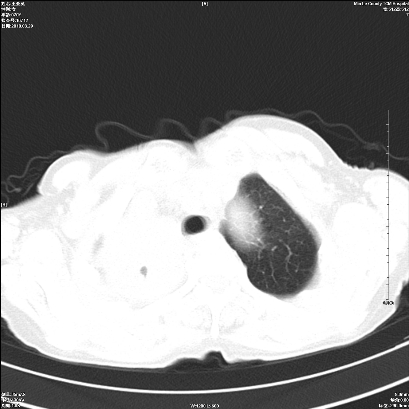

标题: CT25424:女性,70岁,胸闷、咳嗽月余。 [打印本页]

1 右肺门占位伴上叶不张 2 有肺多发感染 3 肝脏转移? 建议增强

1、右侧中央型肺癌伴右肺上叶不张建议支气管镜检   2、右肺中叶及下叶陈旧性病灶   3、肝内多发低密度影,肝内多发转移不除外,建议ct增强!

1)考虑右肺中央型肺癌伴右肺上叶肺不张,右肺门淋巴结转移;建议行支纤维镜检查。2)右肺中叶、下叶及左肺上叶舌段感染性病变。3)肝内多发低密度影,不排除转移瘤可能;建议行ct增强扫描检查。

ct所见:右肺上叶肺不张,呈软组织密度影向肺门区聚拢,其内可见含气段支气管及细支气管影,病灶内尚可见钙化结节。右肺上叶支气管狭窄,段支气管壁可见钙化。右肺下叶背段、右肺中叶见不规则小片絮状影及纤维条索影,形态较僵硬。右肺中叶胸膜旁可见多个小结节影。纵膈内见钙化淋巴结。